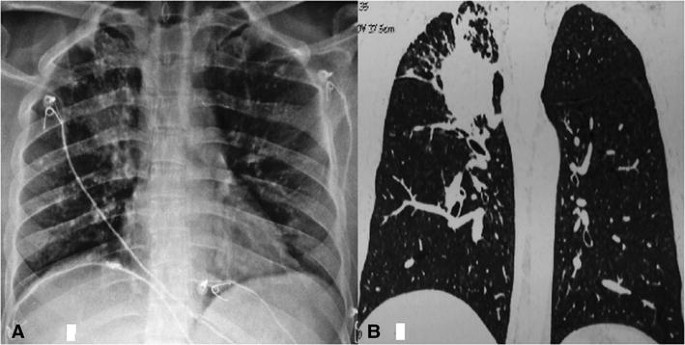

Визуализация и диагностика неинвазивного аспергиллеза с помощью КТ

Раздел: Необычные решения